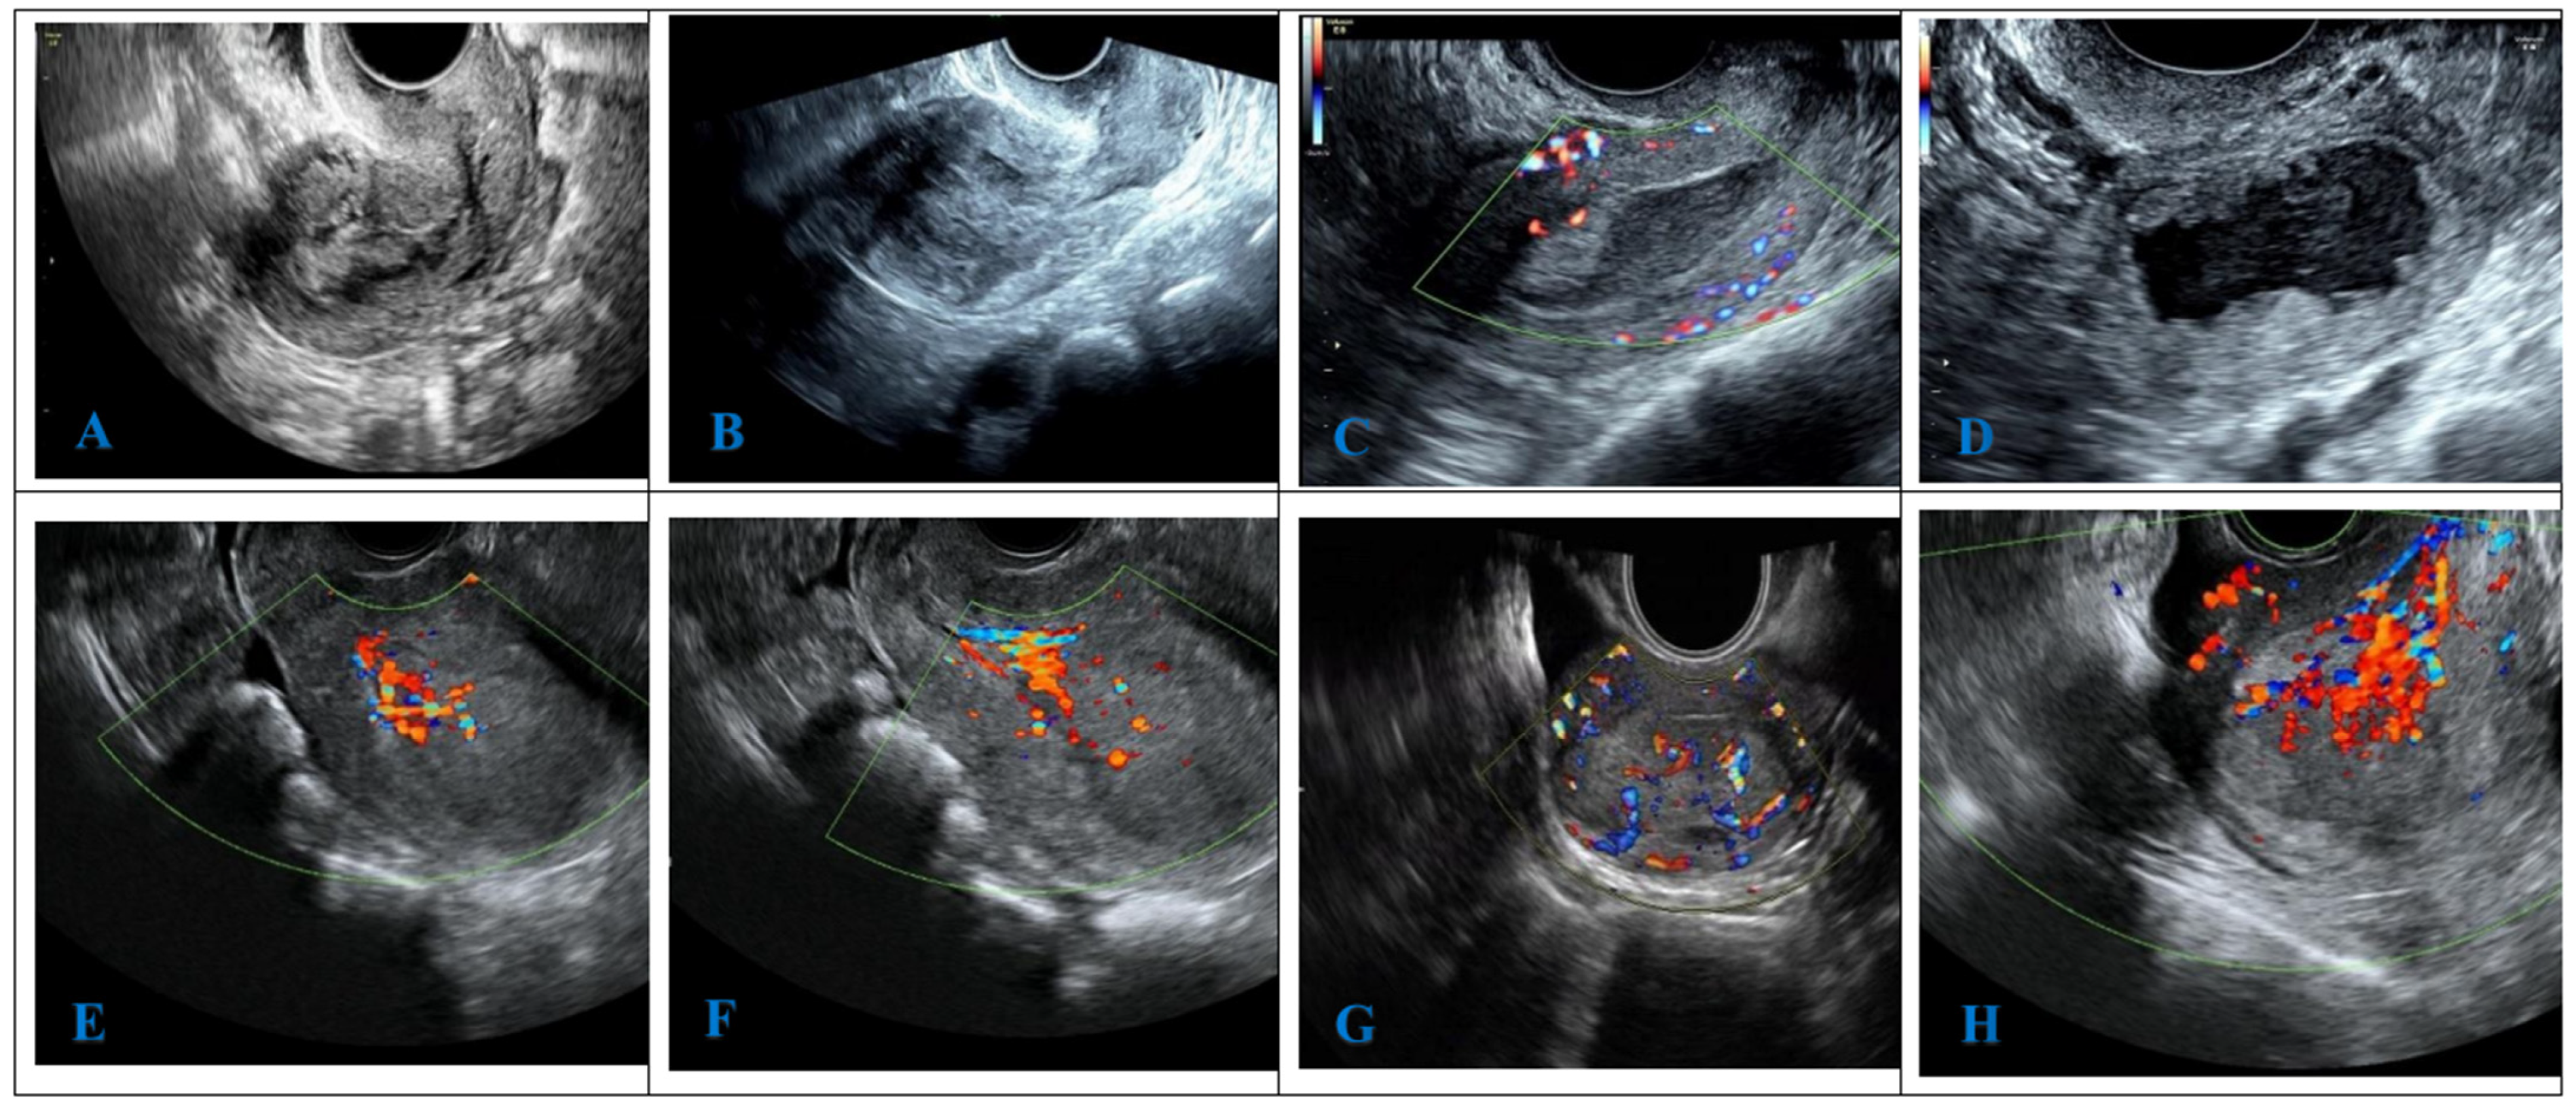

2.8. Ultrasonic Image Analysis